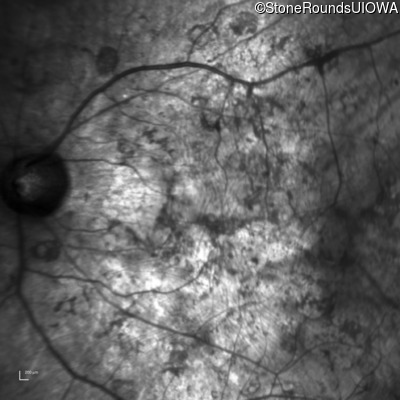

Infrared Fundus Photograph - Left - Hand Motion

Exemplar